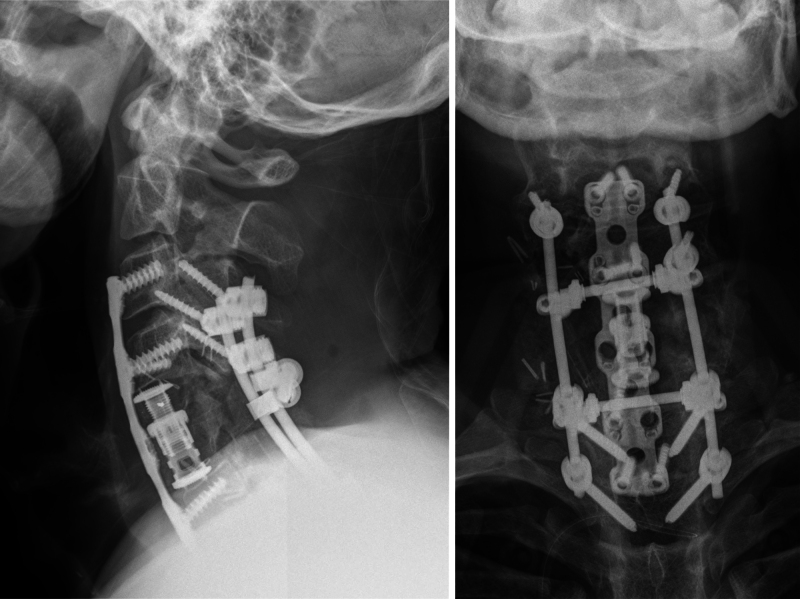

Observations: Here, the authors present the case of a patient who underwent an initial subtotal resection and adjuvant proton beam radiation therapy. Subsequent salvage surgery with aggressive resection was planned in an interdisciplinary setting, resulting in complete resection without recurrence. Despite incomplete resection initially, this case represents an example for reconsidering salvage surgery in an interdisciplinary setting and center of expertise even for cases with residual tumor burden.

Lessons: By highlighting the current literature and setting this clinical case in this context, the authors present a case with a 10-year long-term follow-up, showing that surgical salvage therapy is a possible treatment path with predictable surgery-related morbidity in patients with spinal chondrosarcomas. https://thejns.org/doi/10.3171/CASE25317.